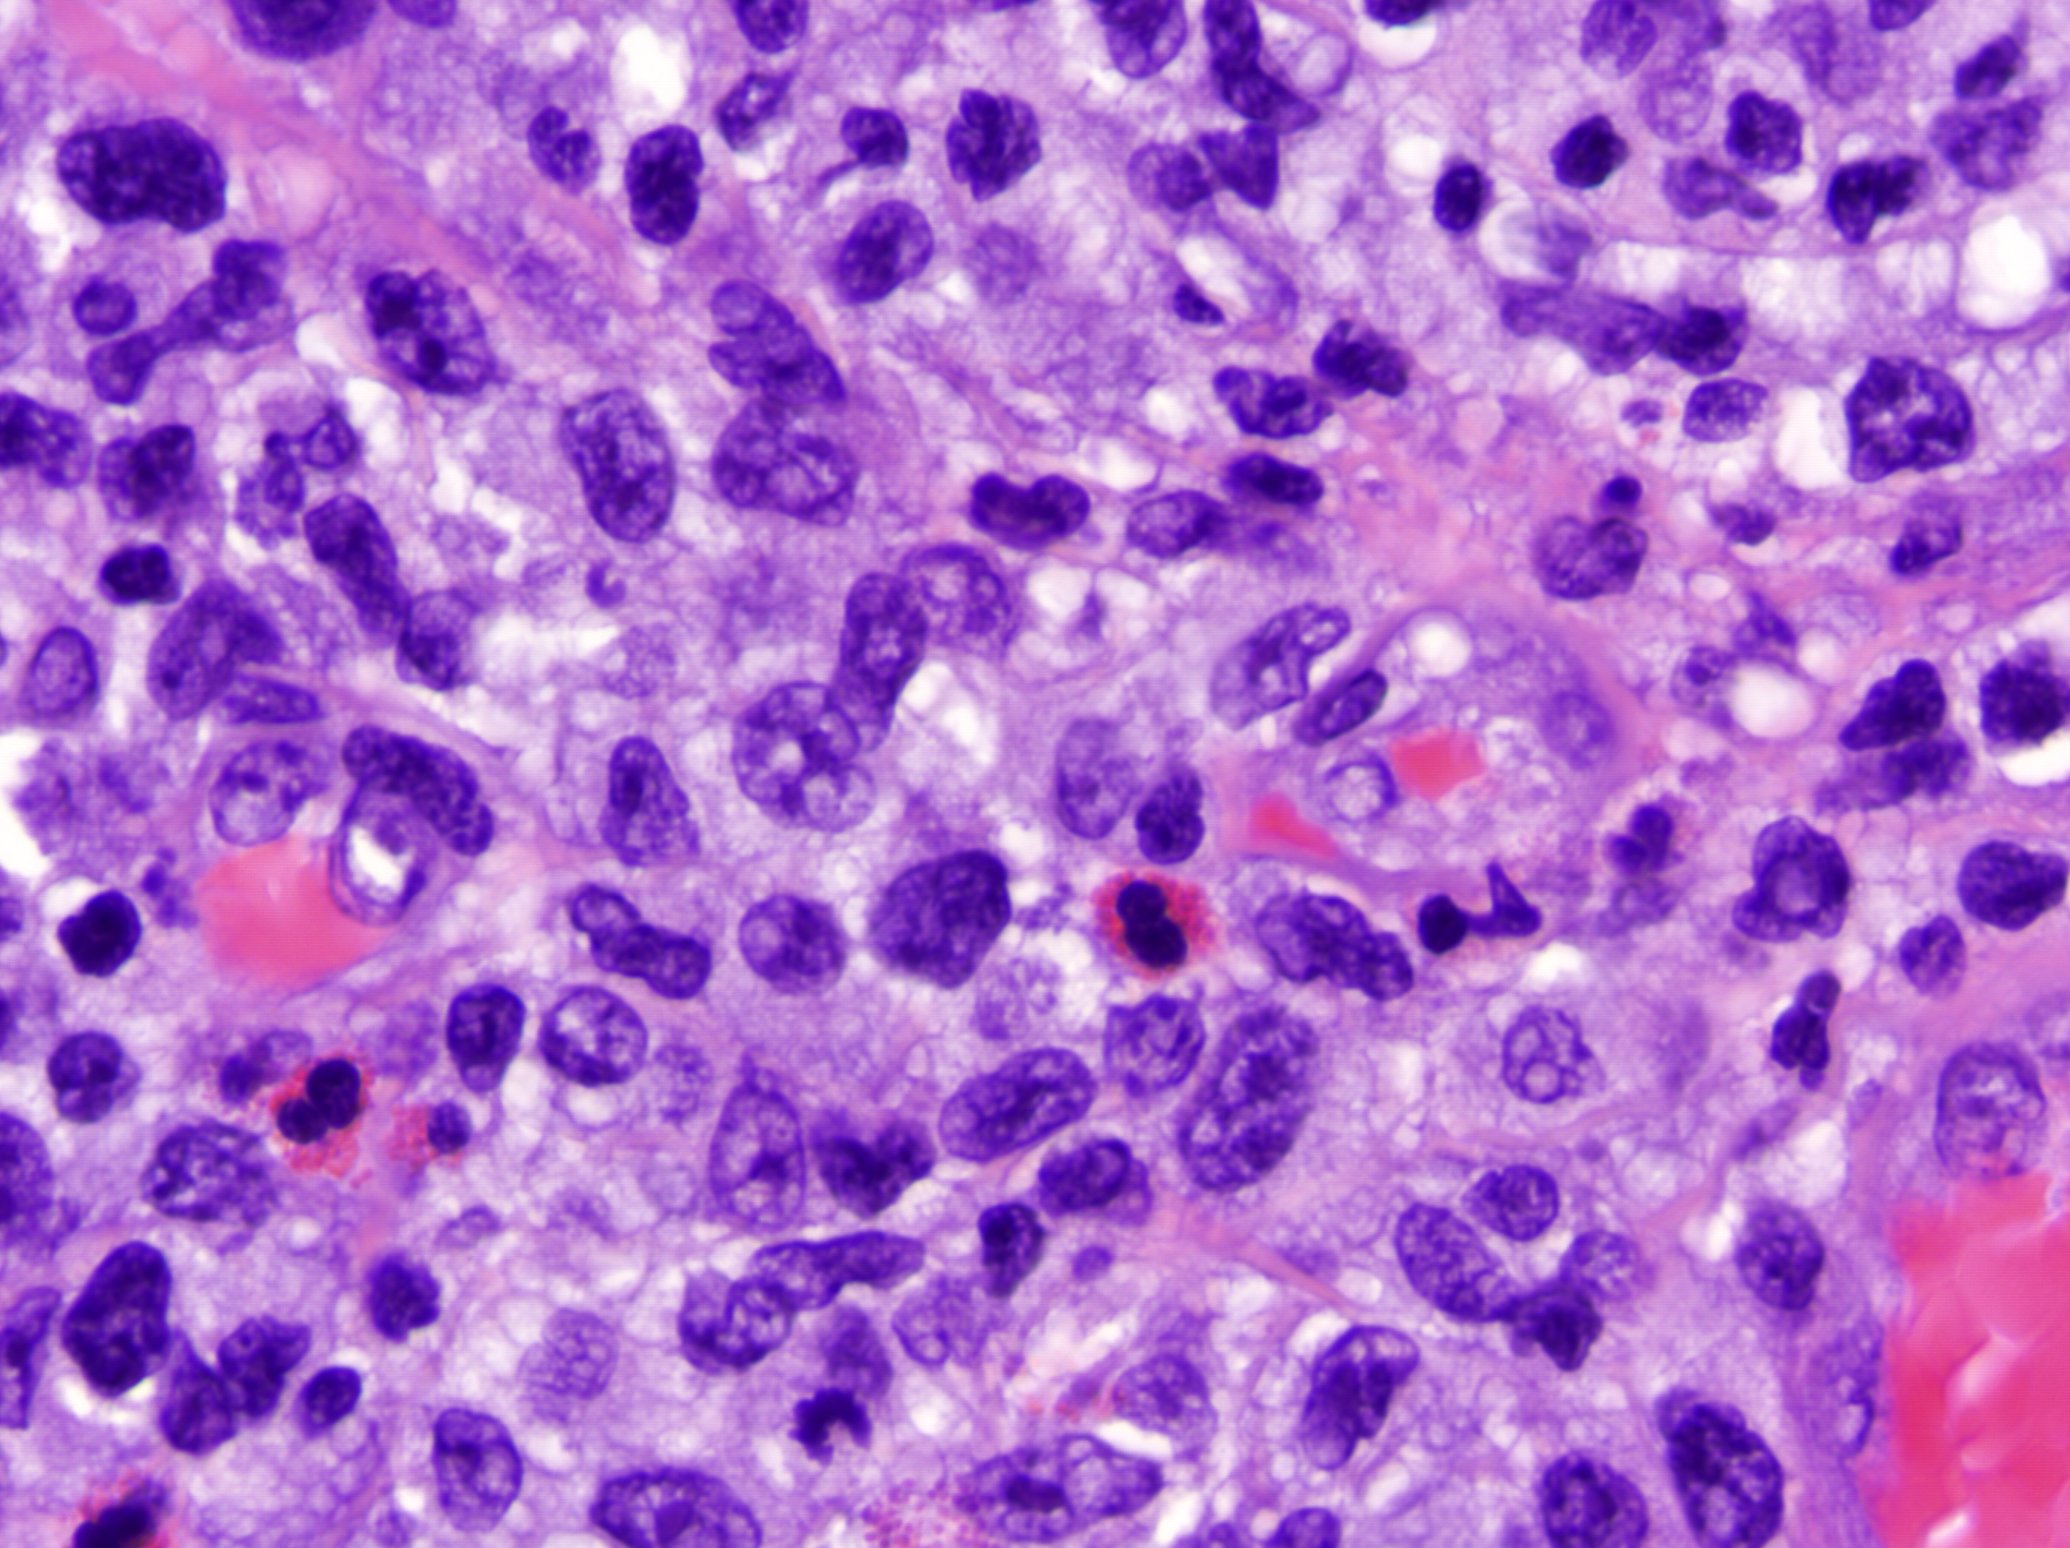

Microscopic (histologic) description

- Lymphomatoid papulosis is characterized by a wedge shaped pattern, with a wide superficial base and the tip at the bottom, usually deep dermis and less frequently into the subcutaneous tissue

- The most characteristic appearance is the presence of few to numerous large cells with a Hodgkin or Hodgkin-Reed Sternberg admixed with a reactive background of small lymphocytes and less frequently eosinophils, plasma cells and histiocytes

- The microscopic appearance and immunophenotype of large cells is variable and led to subclassification of lymphomatoid papulosis into different categories (J Am Acad Dermatol 2016;74:59, Blood 2019;133:1703, Semin Diagn Pathol 2017;34:22, J Am Acad Dermatol 2013;68:809, J Am Acad Dermatol 2012;66:928, Am J Clin Pathol 2003;119:731, Am J Surg Pathol 2010;34:1168, Am J Surg Pathol 2013;37:1)

- Type A: wedge shaped and extensive lymphoid infiltrate with neutrophils, eosinophils and histiocytes; CD30+ cells are scattered and the overall histologic appearance mimics classic Hodgkin lymphoma

- Type C: sheets of large cells, uniformly positive for CD30, with or without epidermotropism and few admixed inflammatory cells; the lesion mimics primary cutaneous anaplastic large cell lymphoma

Microscopic (histologic) images

Contributed by Roberto N. Miranda, M.D.